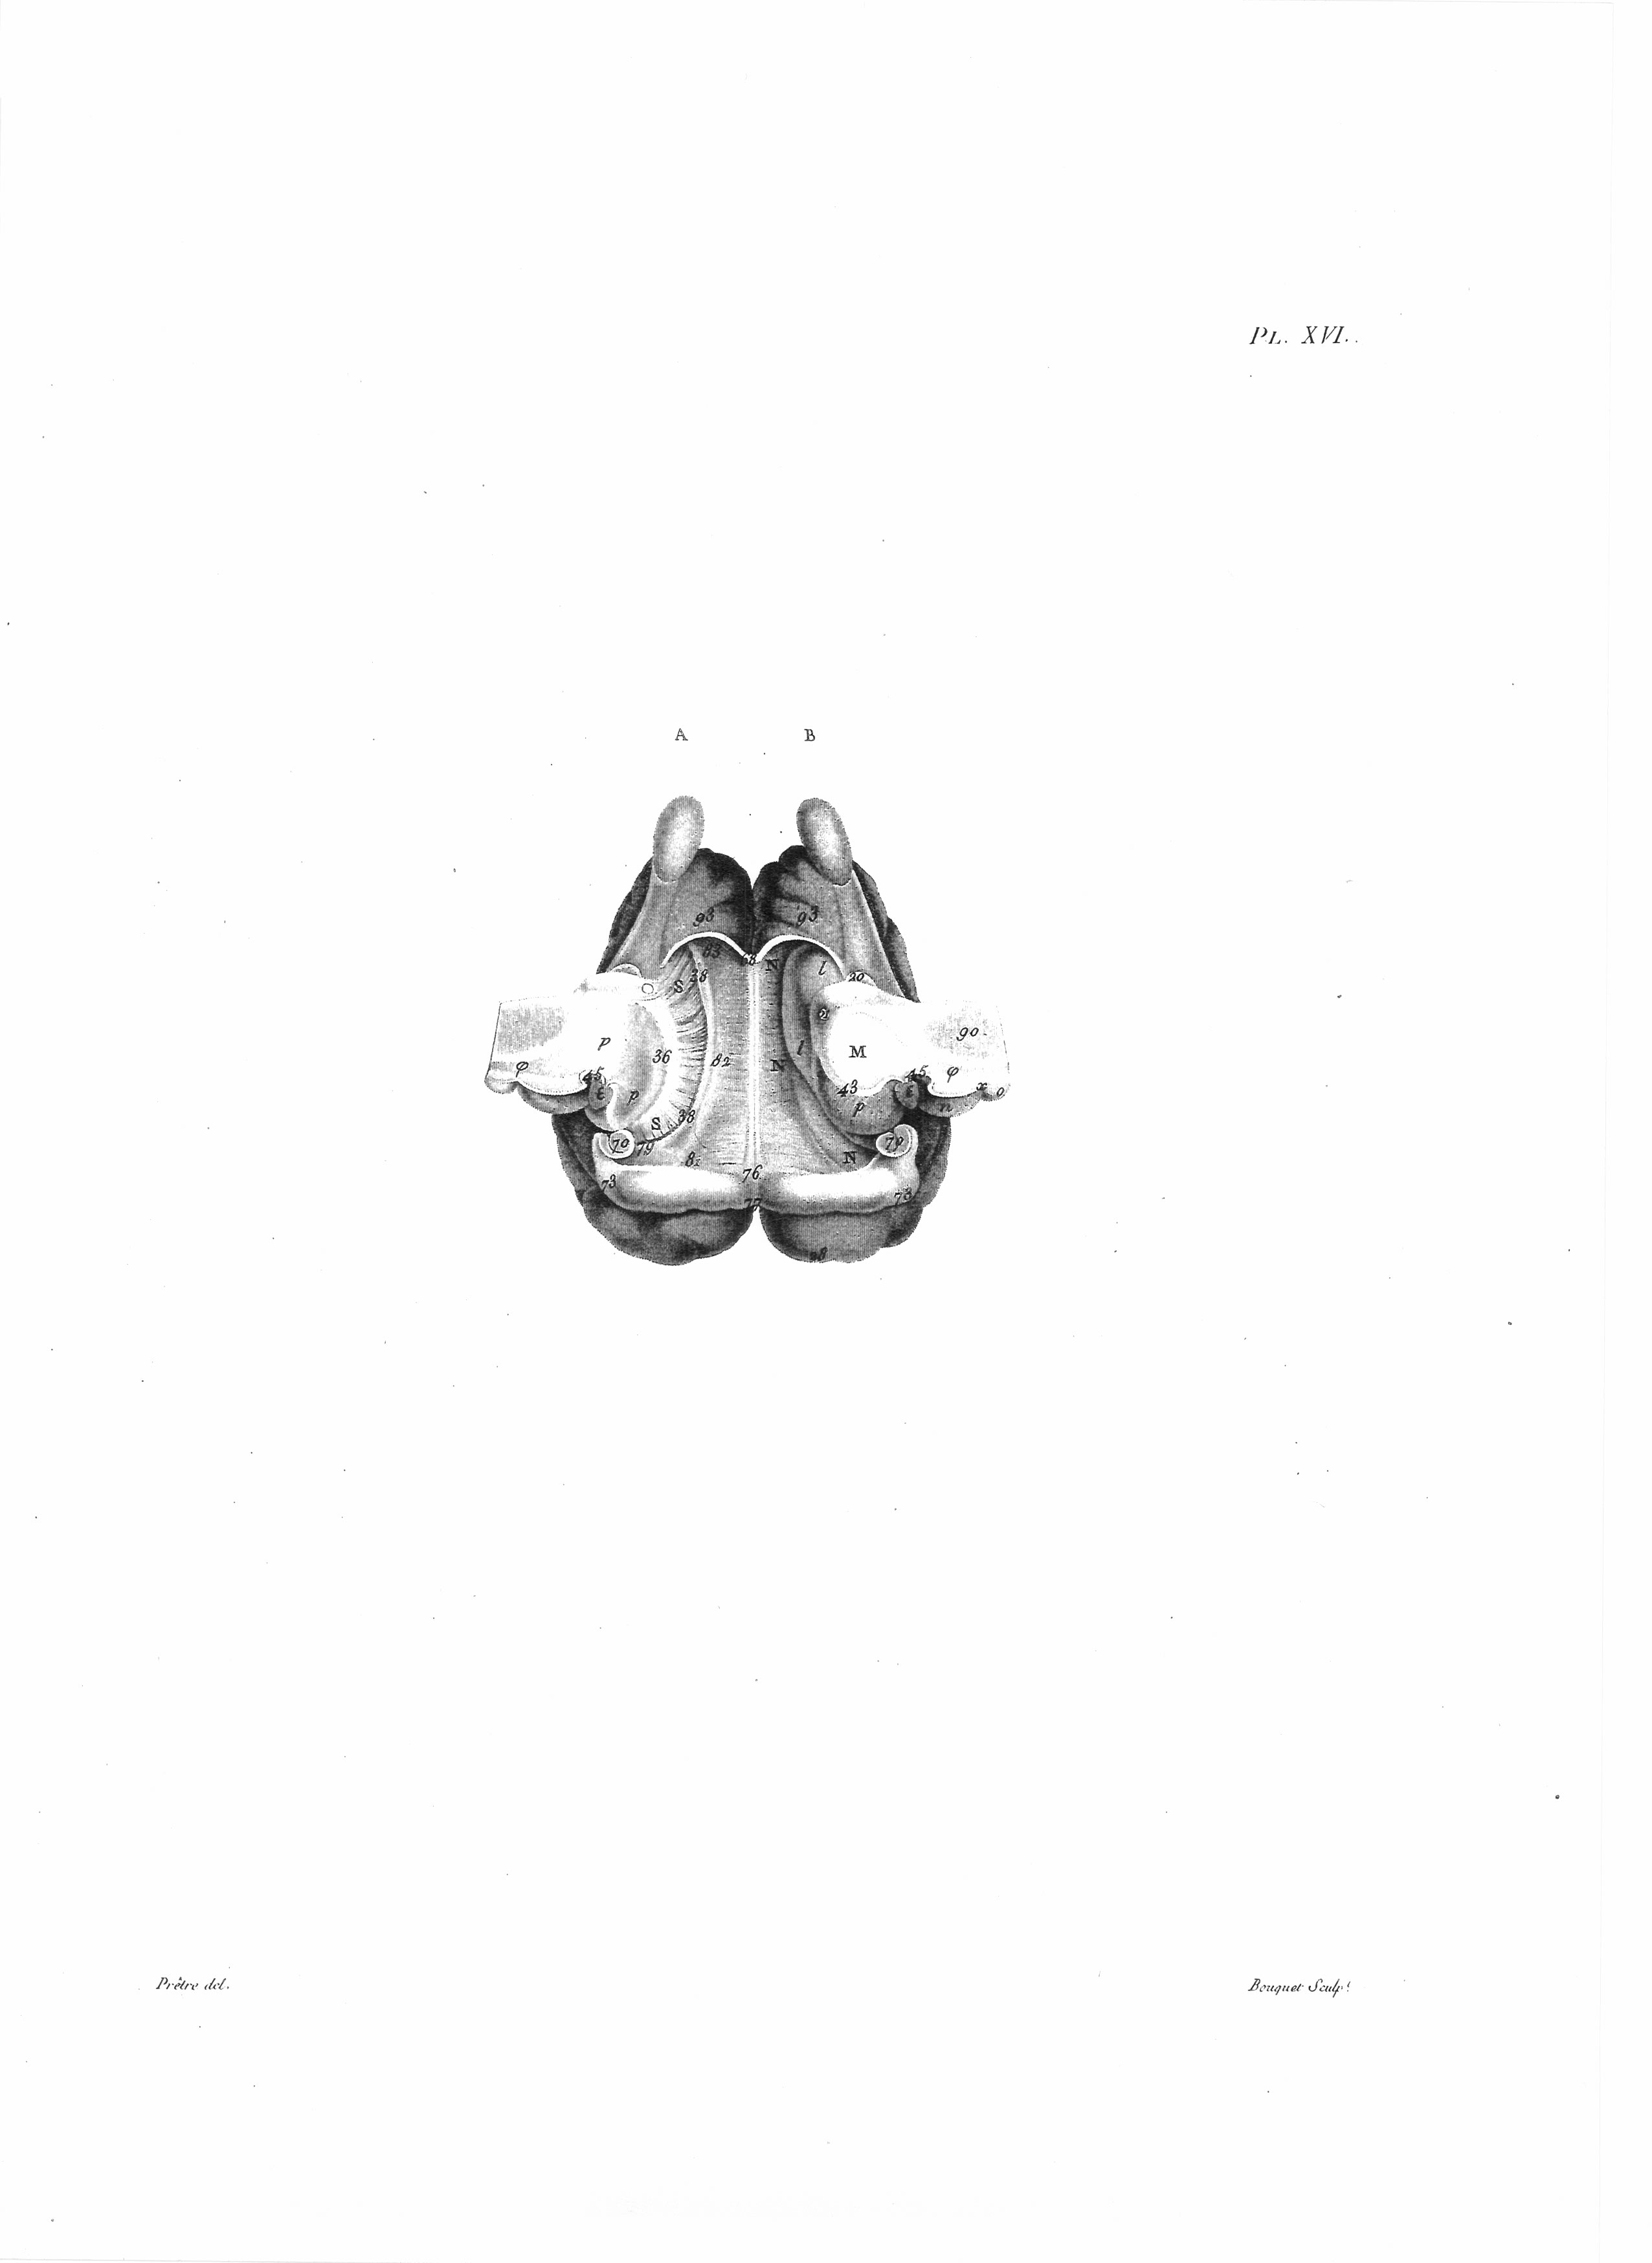

Gall: Plates

Gall, F. J. (1818). Anatomie et physiologie du système nerveux en général, et du cerveau en particulier, Avec des observations sur la possibilité de reconnoître plusieurs dispositions intellectuelles et morales de l´homme et des animaux, par la configuration de leurs têtes.

Librairie Grecque-Latine-Allemande, Vol. 3, I-XXXV u. 1-379 100 planches.